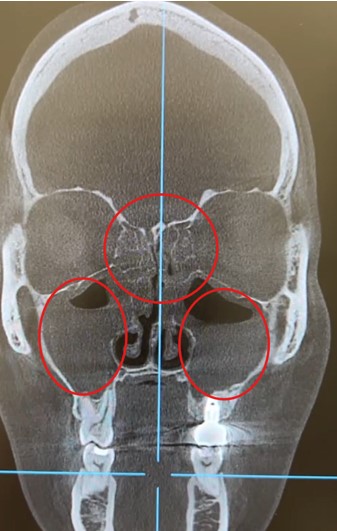

КТ-снимок (коронарная проекция): красными кружкам указаны области тотального снижения пневматизации в верхнечелюстных и решетчатой пазухах, характерные для пансинусита.